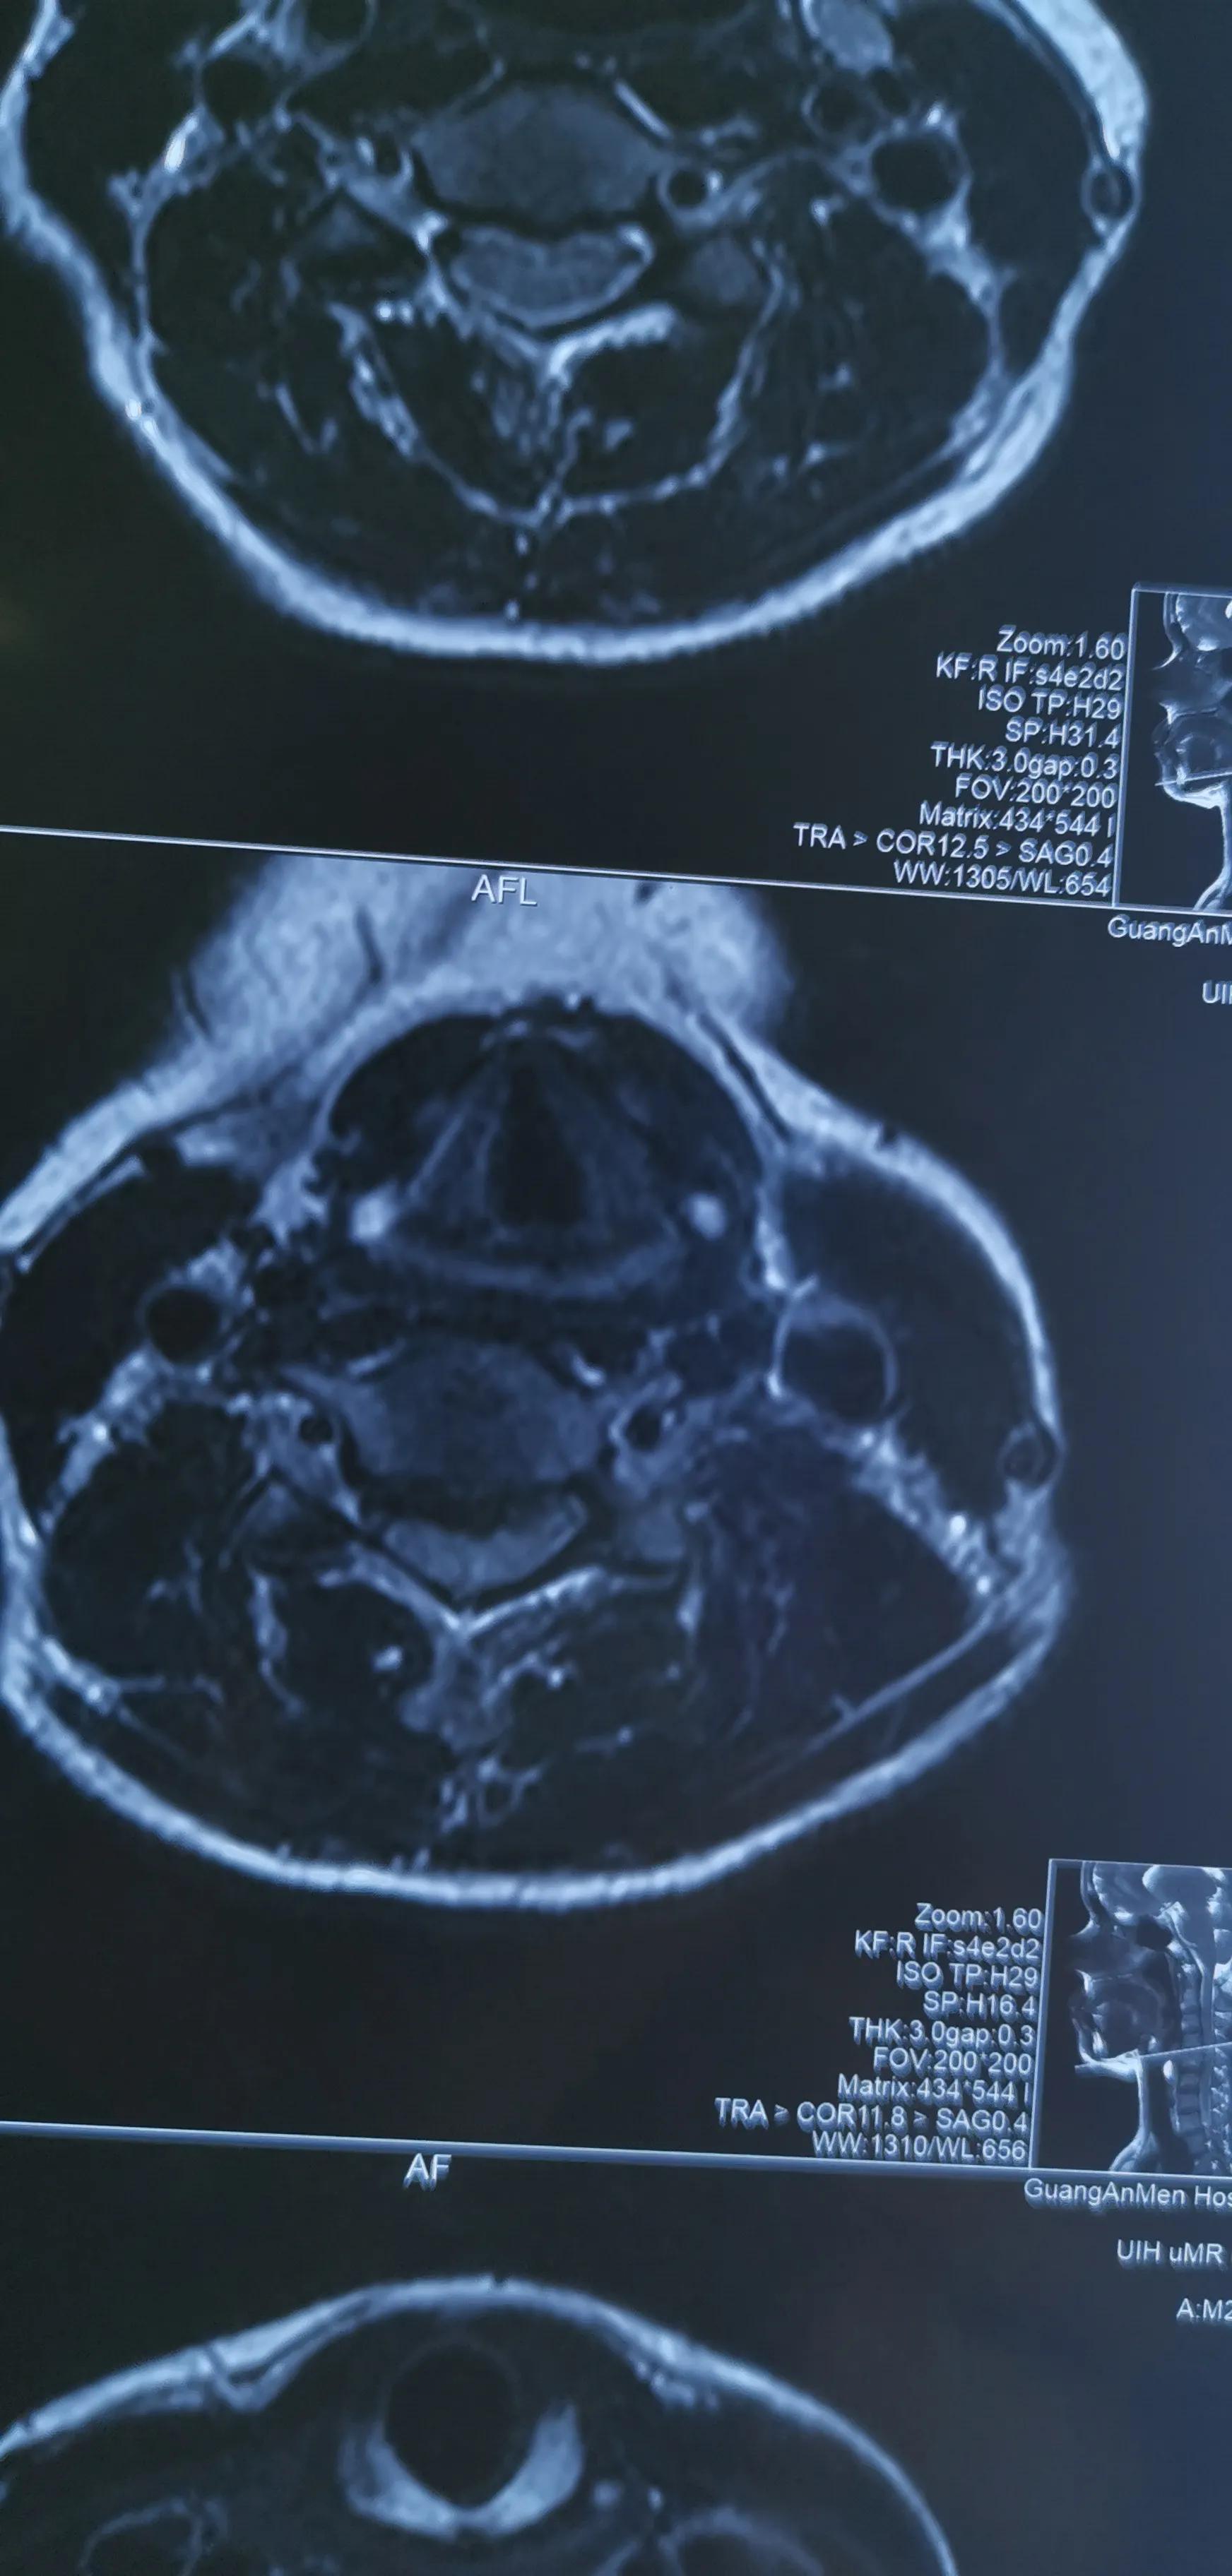

43岁女性,颈肩部疼痛严重伴左侧上肢放射痛无力,mri提示C4/5,C5/6椎间盘突出,CT提示钙化。予前路C5椎体次全切除,椎间盘摘除,椎间钛笼植骨融合钢板内固定,术后疼痛基本消失,肌力逐渐恢复,麻木缓解。

对这类椎间盘突出钙化的患者如果疼痛严重或伴肌力下降或行走不稳,提示压迫神经或脊髓,不宜推拿,可手术减压,效果显著。